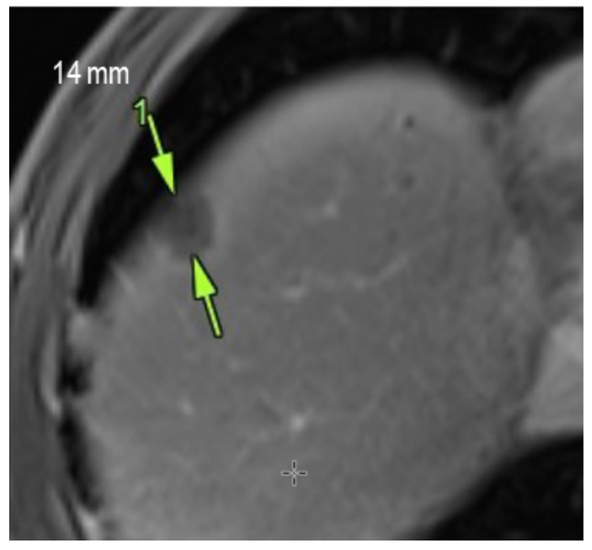

In this study, we describe a patient with advanced-stage prostate cancer and extensive bone metastases who responded positively to our personalized peptide-based immunization therapy (BITAP). Administered as a monotherapy, BITAP was associated with regression of both metastatic and primary tumor lesions, stabilization of PSA levels, and only mild, short-term side effects.